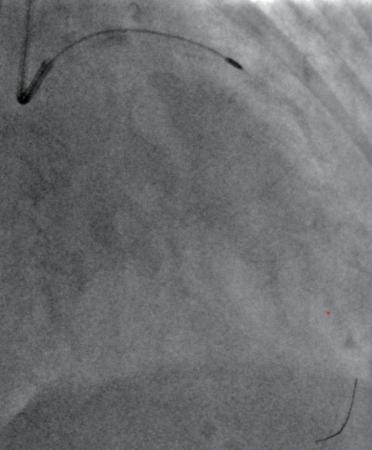

(1)常规经桡动脉穿刺行冠状动脉造影(图1-3-1)。

图1-3-1 冠状动脉狭窄造影